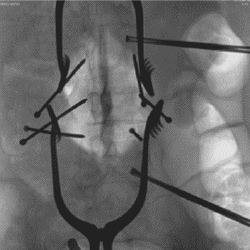

DSA

The DSA and roadmap functions make it suitable for intravascular procedures.